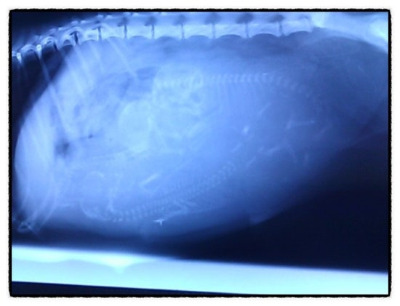

새끼들이 잘 자라고 있는지 X-ray를 통해 확인하기도 했다.

쫑이 아가들의 X-ray 사진